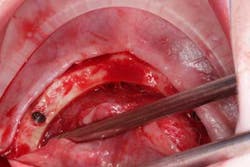

Surgery commenced. Implants on the lower arch were placed first (figures 7 and 8) and then we switched to the maxillary. The teeth were removed (figures 9 and 10) and the ridge was evened out (figures 11-13). The implants were aligned with the denture (figure 14) and then placed accordingly (figures 15-17). Healing caps were put on, and we were ready to start the restorative phase (figures 18-19).